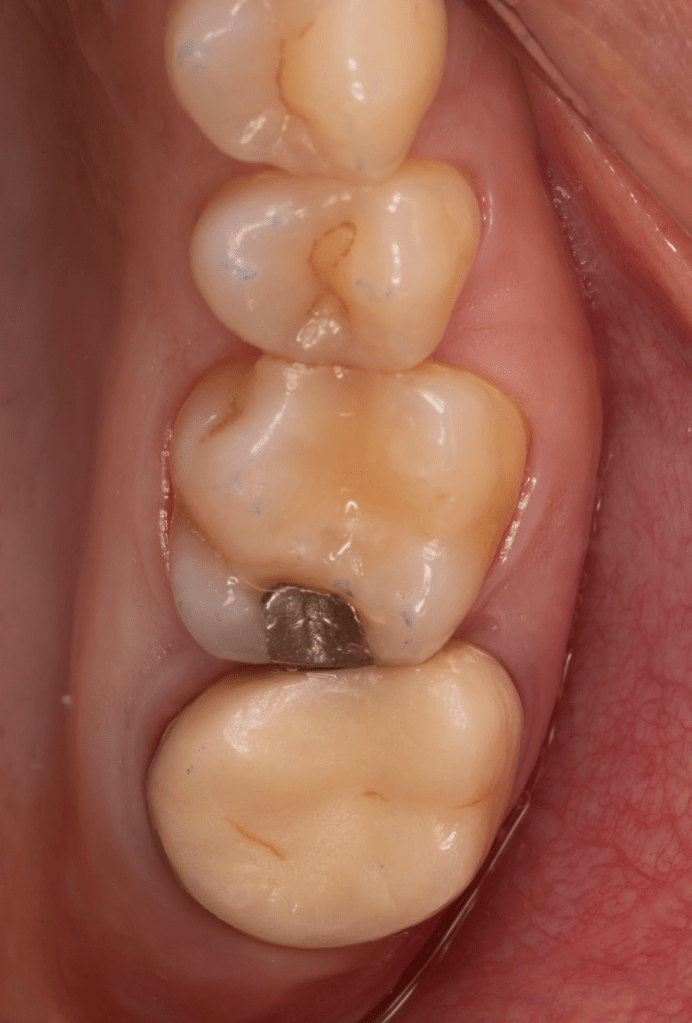

Fisura, remoción amalgama para explorar